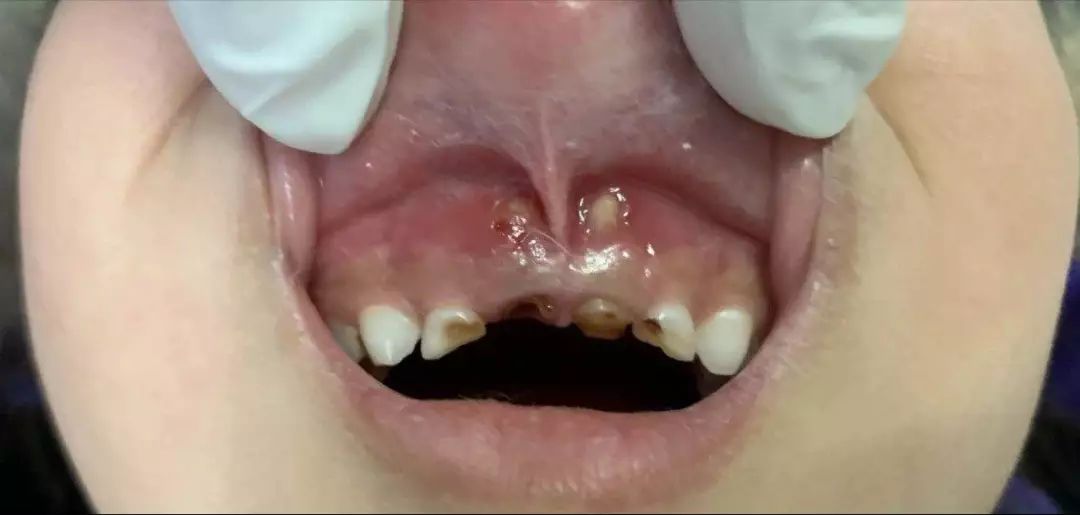

乳牙根尖周炎破壞牙槽骨并穿破粘膜

乳牙根穿破粘膜并形成創(chuàng)傷性潰瘍

而且有這樣的一種現(xiàn)實(shí),哪怕全口牙齲壞也鮮有家長(zhǎng)為此主動(dòng)去看牙醫(yī),更多的是當(dāng)孩子出現(xiàn)了劇烈牙痛或者牙齦上長(zhǎng)出了令家長(zhǎng)們驚恐的如圖示腫物(恐癌心理)才被迫就診,這是一種中國(guó)式特色——反正乳牙都是要換掉的,單純齲齒治不治無(wú)所謂。

1、嚴(yán)重的也是常見的危害,并不是齲齒本身,而是齲齒進(jìn)展帶來(lái)的并發(fā)癥,它可進(jìn)一步發(fā)展為牙髓炎(劇烈牙痛)、根尖周膿腫,瘺管,甚至擴(kuò)散至頜周間隙感染,嚴(yán)重者會(huì)形成頜面部蜂窩織炎甚至引起敗血癥,可危及生命。中國(guó)大部分三甲醫(yī)院口腔科,每年都免不了收治些重癥牙源性間隙感染的患兒住院,無(wú)一不是來(lái)源于一顆小齲齒的慢性進(jìn)展。

2、對(duì)恒牙及恒牙列的影響。乳牙的齲齒引起慢性根尖炎癥長(zhǎng)期刺激其根周的恒牙胚,導(dǎo)致恒牙萌出后即出現(xiàn)釉質(zhì)發(fā)育不全,稱為“特納牙”。另外,乳牙因齲早失后可致恒牙換牙時(shí)失去咬合誘導(dǎo)而長(zhǎng)得亂七八糟,得依靠后期牙齒矯形來(lái)糾正,費(fèi)時(shí)費(fèi)力費(fèi)神費(fèi)錢。